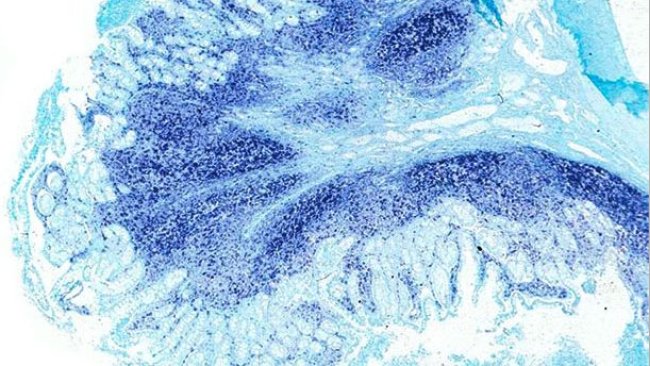

Comment le PCV2 contribue aux troublles intestinaux ?

Récemment on a émis l’idée que le PCV2 est capable de produire de la diarrhée chez les porcs et on a proposé la maladie entérique associée au PCV2 (PCV2-ED) comme une entité séparée à l’intérieur des maladies associées au circovirus porcin (PCVDs).